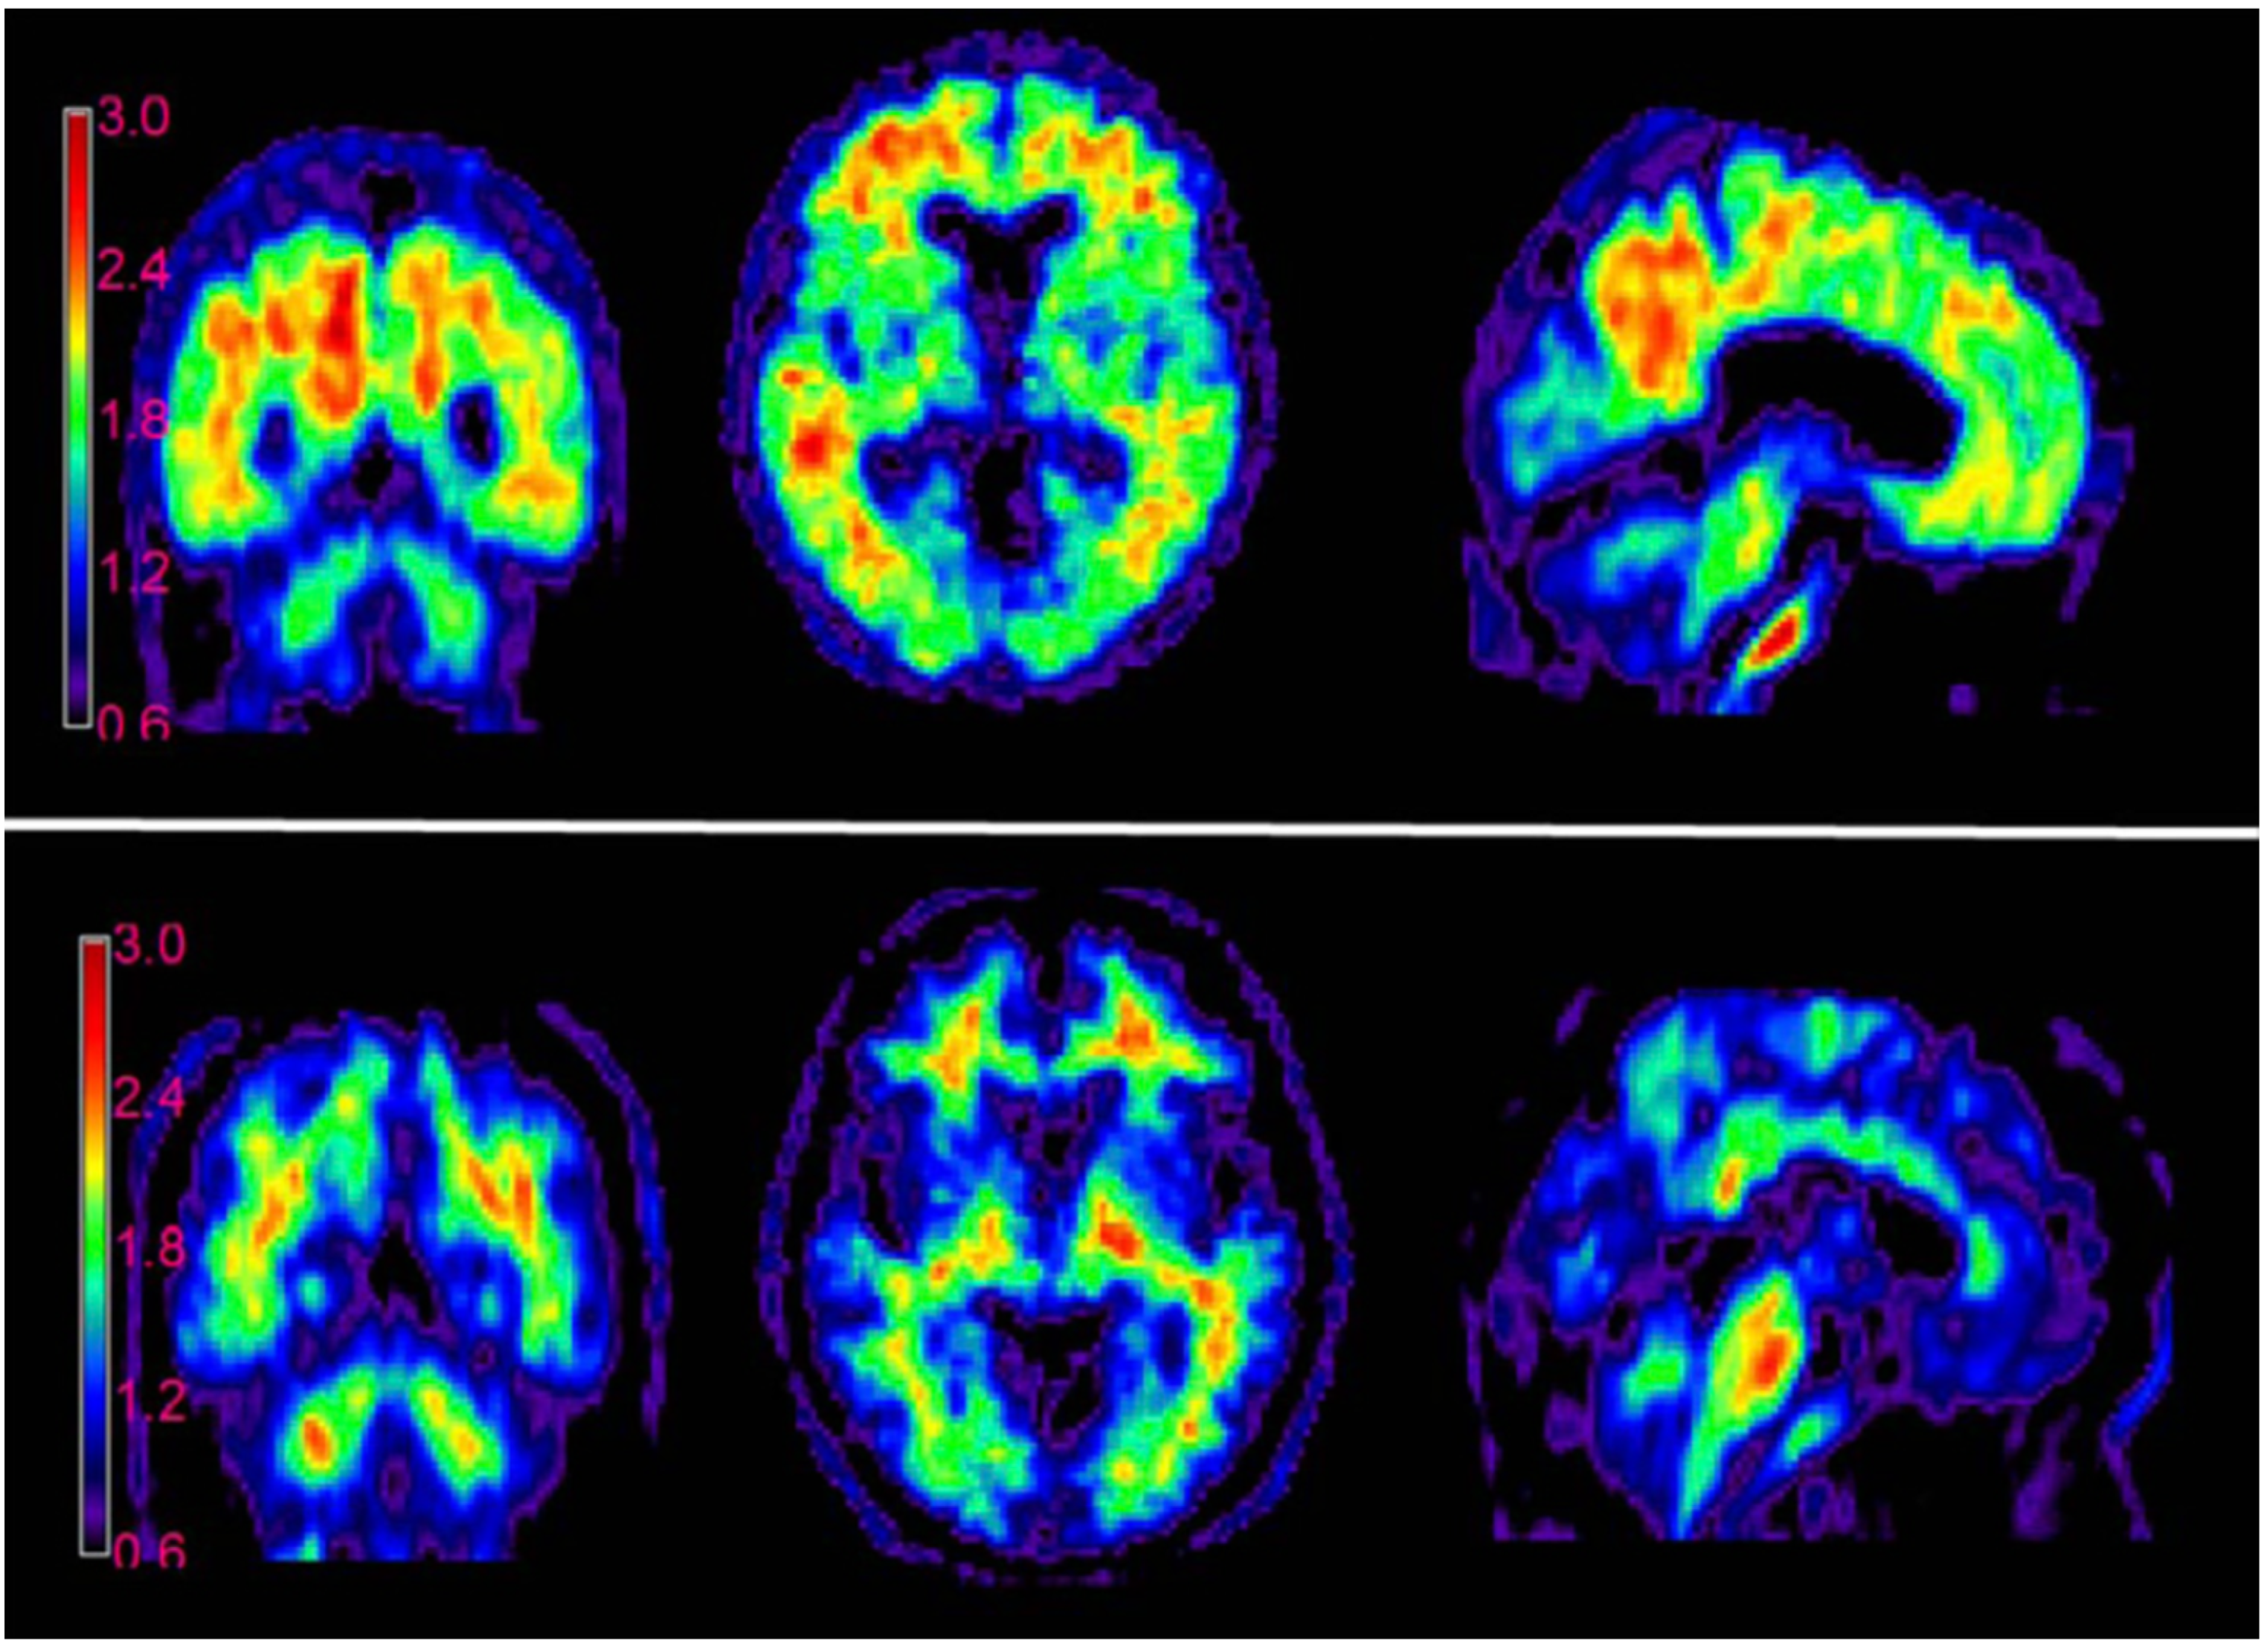

- Yanagisawa, D.; Amatsubo, T.; Morikawa, S.; Taguchi, H.; Urushitani, M.; Shirai, N.; Hirao, K.; Shiino, A.; Inubushi, T.; Tooyama, I. In Vivo Detection of Amyloid β Deposition Using 19F Magnetic Resonance Imaging with a 19F-Containing Curcumin Derivative in a Mouse Model of Alzheimer’s Disease. Neuroscience 2011, 184, 120–127. [Google Scholar] [CrossRef] [PubMed]

- Yanagisawa, D.; Taguchi, H.; Ibrahim, N.F.; Morikawa, S.; Shiino, A.; Inubushi, T.; Hirao, K.; Shirai, N.; Sogabe, T.; Tooyama, I. Preferred Features of a Fluorine-19 MRI Probe for Amyloid Detection in the Brain. J. Alzheimer’s Dis. 2014, 39, 617–631. [Google Scholar] [CrossRef] [PubMed]

- Yanagisawa, D.; Ibrahim, N.F.; Taguchi, H.; Morikawa, S.; Tomiyama, T.; Tooyama, I. Fluorine-19 Magnetic Resonance Imaging for Detection of Amyloid β Oligomers Using a Keto Form of Curcumin Derivative in a Mouse Model of Alzheimer’s Disease. Molecules 2021, 26, 1362. [Google Scholar] [CrossRef] [PubMed]